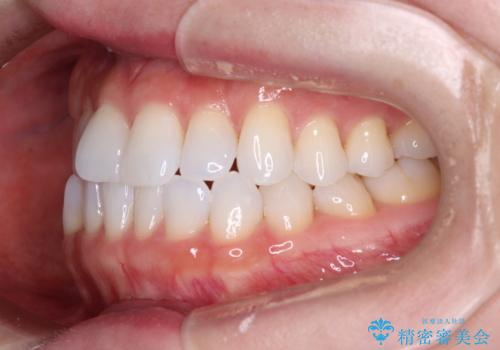

前歯のデコボコをインビザラインで綺麗に

- 上下前歯の叢生を気にして来院された患者様です。

インビザラインでの治療を希望されていて、デコボコの程度が中等度であり、安価なパッケージにて対応可能と判断されたため、インビザライン・モデレートを用いて矯正治療を行うこととしました。